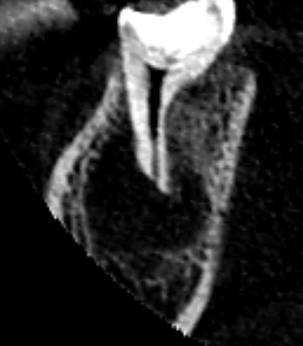

下顎第二大臼歯の初診時の矢状断のCT画像です。